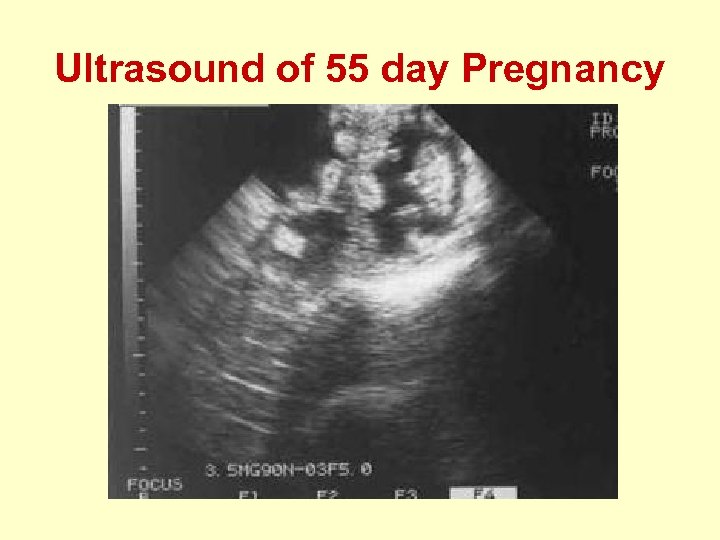

Ultrasound of 55 day Pregnancy

Pregnancy Diagnosis • Can reduce costs, increase income, and maximize returns on available inputs. • Several possibilities, each with advantages and disadvantages. – Doppler Ultrasound – “A Mode” Ultrasound – Blood Hormone Assay

Doppler Ultrasound • Expensive to purchase. • Delicate and only somewhat portable. • Requires extensive training and practice to use accurately. • Accurate and early results. • Use with multiple species and multiple functions. • May show number of fetuses. • Slower to operate accurately.